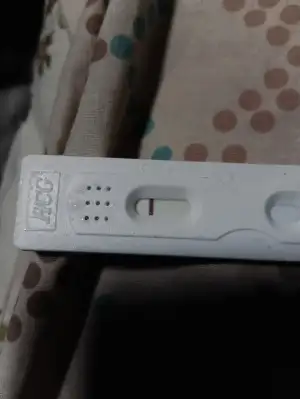

Gebelik testim bu şekilde çıktı

bi gölge gördüm sanki. Testi yaptıktan ne kadar sonra çektiniz fotoğrafıKızlar yumurtlama günümü ovulasyon testi ile takip ettim ovulasyona göre bata 5 gün var normal adet zamanına göre 10 gün sizce durum nedir ?

Fotoğrafı 20 dk sonra çektim. Ama ilk anda çok silik gölge gibi oldu zaten. Emin olmadığım için de kimseye gösteremedimbi gölge gördüm sanki. Testi yaptıktan ne kadar sonra çektiniz fotoğrafı

Test birgebeningünlüğünü mü? Eğer o ise ilk 10 dk geçerliKızlar yumurtlama günümü ovulasyon testi ile takip ettim ovulasyona göre bata 5 gün var normal adet zamanına göre 10 gün sizce durum nedir ?

Evet bir gebenin günlüğünün testi. Ama testin üstünde 10 dk de sonuç çıkar. 20 dk sonra ki sonucu dikkate almayın diyordu ben yaptım 5 dk içinde bu gölgelik oluştu. Ben sadece emin olmadığım için atmadım ve 20 dk sonra testin fotosunu çektimTest birgebeningünlüğünü mü? Eğer o ise ilk 10 dk geçerli

Olabilir yani sonucun da benim demek istediğim test 5 dk de bu sonucu gösterdi ama ben 20. Dk de çektim fotoyu Ama doğru mu gösterdi yoksa başka birşey mi anlamadımEbru hanım bana gebelik testi 10 dk- ovulasyon testinde 20 dk sonuç süresi demişti

Bu da bugün yaptığım test Yine 5 dk de yerini belli eden bir çizgi oluştu sonra durdukça koyulaştı. Hatta kuruma çizgisi olabilir diye düşünüp testi ıslattım ama çizgi hiç dağılmadı da kaybolmadı da. Anlam veremedim yinee